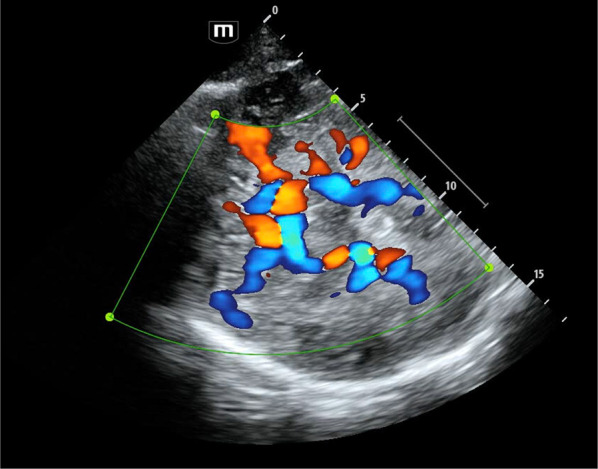

经颅超声作为一种有用的床边监护工具和无创诊断设备在危重病人中得到了广泛的认可。经颅超声本身的能力也在不断提高,加上对生理学的理解不断提高,使人们能够深入了解常常被床边重症监护临床医生所掩盖的病理生理过程。经颅超声在其无创、快速和关键的复合血流速度中心(非压力中心)信息方面仍然是独特的。经颅超声装置的移动性对需要多器官支持治疗的大部分不能移动的危重病人具有特别的价值。在这篇综述中,我们讨论了一些更现代的复合技术的重要起源,并强调了相关的主要关键概念,同时注意到令人兴奋的前沿可能性。

Transcranial ultrasound is gaining widespread recognition as a useful bedside monitoring tool and non-invasive diagnostic device in the critically ill patient. The capabilities of transcranial ultrasound are themselves ever-increasing, and this, combined with improved physiological understanding, affords insights into pathophysiological processes often concealed from the bedside critical care clinician. Transcranial ultrasound remains unique in regard to its non-invasive, rapid, and critically composite blood flow velocity-centric (not pressure-centric) information. The mobility of transcranial ultrasound devices is of particular value to the largely immobile critically ill patient requiring multiple organ supportive therapies. In this review, we discuss some important origins of more modern composite techniques and highlight relevant major key concepts, whilst noting exciting frontier possibilities.